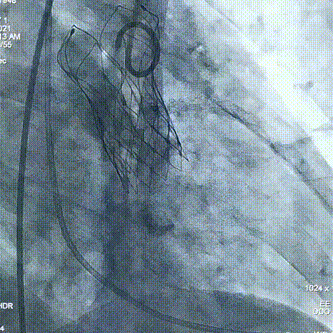

术中操作

球囊预扩

瓣膜定位

经评估后植入左主干烟囱支架